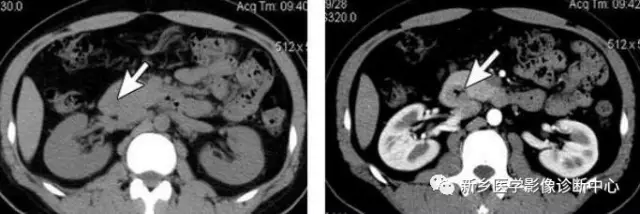

13 肠梗阻

文章图片

1.肠梗阻:中腹部多发阶梯状 , 马蹄状液平 。 2.空肠不全性梗阻 。

1.空肠不全性梗阻:空肠扩展呈弹簧状 。 2.空肠机械性梗阻:弹簧征